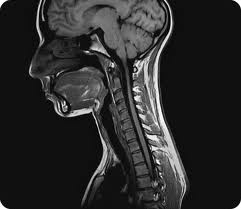

When you see your doctor to help you with your neck arthritis, you will be asked to rotate your head and move it towards your shoulders as slight pressure is placed on your head. The increased amount of pain that you experience during the test is an indication that there is pressure on the spinal nerve.  Be warned that the significant weakness and numbness can be signs that your nerve roots or even your spinal cord is damaged already. Reduced amount of reflexes is a common indication. You need to undergo an MRI (severe pain of the arm and neck that doesn’t get relieved when treated or numbness of hands or arms) and an X-ray (changes in the spinal configuration or arthritis).  To test for nerve root function, you would have to undergo nerve conduction velocity and EMG.